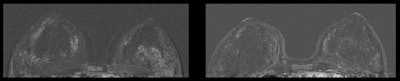

Breast MRI of a 41-year-old patient. The left image is without an IUD in place, while the right image shows increased parenchymal enhancement in the same patient 27 months after IUD placement.

Breast MRI of a 41-year-old patient. The left image is without an IUD in place, while the right image shows increased parenchymal enhancement in the same patient 27 months after IUD placement. Breast MRI of a 45-year-old patient. The left image is with an IUD in place, while the right image is from the same patient 32 months after IUD removal.